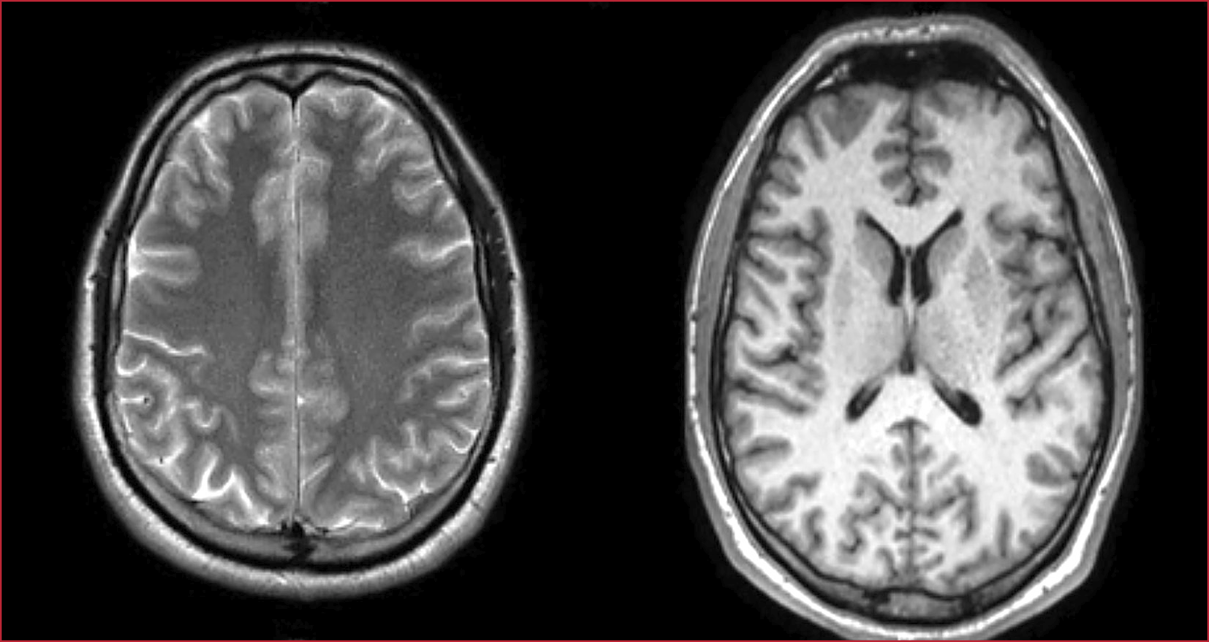

Los

resultados de los análisis bioquímicos al ingresar son normales. La TAC, la RM

y la PL no muestran alteraciones (Figura 2, Tabla 1). Resultado negativo para

Figura 2. Caso 2. Resonancia magnética de cerebro. Sin anomalías.